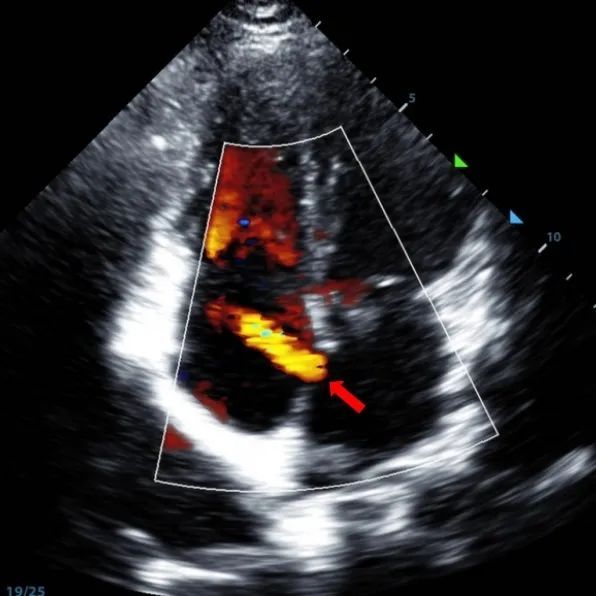

Secundum asd (7.5-7.9mm) ile 9 yaşındaki bir erkek, memosorb BDASD-I 12mm occluder ve 12f dağıtım sistemi kullanılarak tedavi edildi. Komplikasyonlar veya komorbiditeler ön prosedür olarak belirtilmedi.

Serial echocardiographic follow-ups showed stable device position and favorable cardiac remodeling. Gradual degradation confirmed the occluder's long-term safety and efficacy.